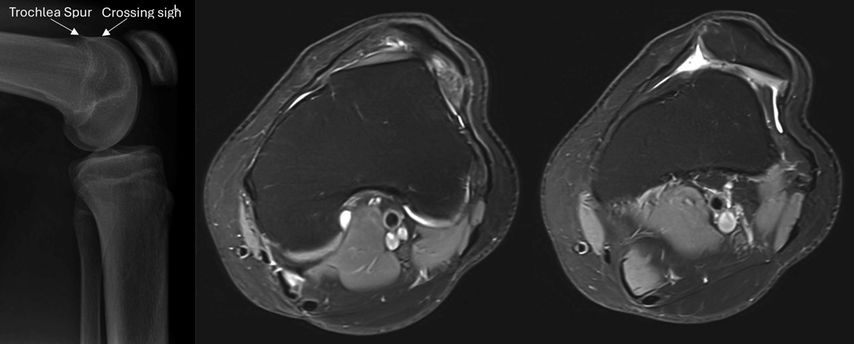

Es besteht eine inverse Korrelation zwischen der Intensität des Traumaereignisses und dem Schweregrad der anatomischen Risikofaktoren. Neben einer strukturierten und fokussierten Anamneseerhebung sowie klinischen Untersuchung erfolgt mittels Standardröntgen und MRI die anatomische Risikostratifikation für eine persistierende Instabilität mitsamt Abklärung eventueller (osteo)chondraler Verletzungen. Im axialen Röntgen können der laterale Trochleainklinationswinkel und der Sulcuswinkel bereits einen Hinweis auf eine Trochleadysplasie liefern. Ihre qualitative Einteilung nach Dejour erfolgt in der streng lateralen Aufnahme mit korrekter Überlagerung der posterioren Femurkondylen sowie in der axialen Schichtbildgebung.18 Die Kriterien im Röntgen sind das Crossing Sign, der supratrochleare Spur sowie die Doppelkontur (Abb. 1). In der am weitesten proximalen axialen MRI-Schicht mit trochlearem Knorpelüberzug entsprechen sie einer abgeflachten respektive flachen Trochlea bzw. einer asymmetrischen Kondylenausprägung im Sinne einer hypoplastischen medialen und konvexen lateralen Trochlea. Typ A (Crossing Sign) wird dabei als milde, die Typen B (Crossing Sign und supratrochlearer Spur), C (Crossing Sign und Doppelkontur) und D (alle drei Kriterien) als schwere Formen eingestuft.

Abb. 1: Laterales Röntgen mit Crossing Sign und Trochlea Spur (links). Daneben MRI einer Trochleadysplasie Typ C, respektive Typ 2, mit abgeflachter Trochlea und hypoplastischem medialem Kondylus sowie deutlicher Lateralisation der Patella

Eine nicht streng seitlich getroffene Aufnahme und die subjektive Interpretation der Klassifikation limitieren ihre Reproduzierbarkeit, was zum Anlass genommen wurde, eine rein MRI-basierte quantitative Einteilung zu erstellen. Bei dieser wird die Trochlea anhand des Sulcuswinkels, des lateralen Trochleainklinationswinkels und der Grösse eines zentralen Bumps im axialen respektive sagittalen MRI in einen Typ 0 (keine Dysplasie), Typ 1 (geringgradig), Typ 2 (mittelgradig) oder Typ 3 (hochgradig) eingeteilt (Tab. 1).